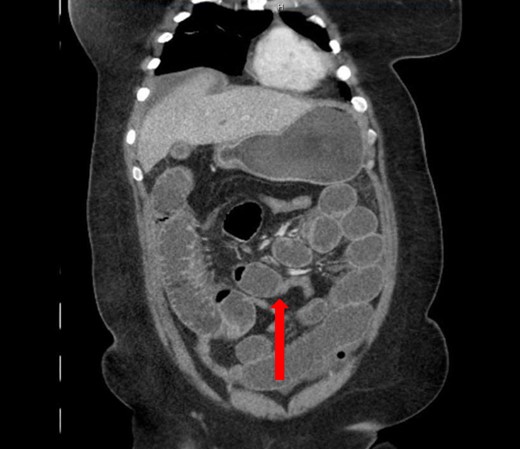

A 40-year-old woman presented to the emergency department with abdominal pain for 4 days. She had previously been seen at an outside hospital 3 days earlier, and was diagnosed with biliary colic. Her pain was constant, and was associated with nausea and vomiting. She had a history of a cesarean section, but no other abdominal surgeries. Her vitals were within normal limits: afebrile at 36.9°C, heart rate 71 beats/minute, blood pressure 143/62 mmHg, respiratory rate 18 breaths/minute, and oxygen saturation 97% on room air. On abdominal exam, she was distended, tender, demonstrated voluntary guarding and was positive for peritonitis. Laboratory values were significant for a white blood cell count of 16.1 K/ul, with 80.2% neutrophils, hemoglobin 14.9 g/dl, hematocrit 45.4%, platelets 349 K/ul and lactic acid 0.9 mEq/L; her chemistry was unremarkable. A computed-tomography (CT) scan of the abdomen and pelvis that was obtained prior to surgical consultation demonstrated the proximal two-thirds of small bowel dilated up to 4 cm, with a sharp transition point in the left mid-abdomen, and collapsed small bowel loops near the cecum. The colon was mostly collapsed. A few distended loops bulged into a paraumbilical hernia, which was 6 cm wide and not the cause of obstruction (Figs 1–3).

Coronal view: arrow pointing to the dumb-bell transition point, where the proximal end of the closed loop small bowel herniated through a hole in the sigmoid epiploica.